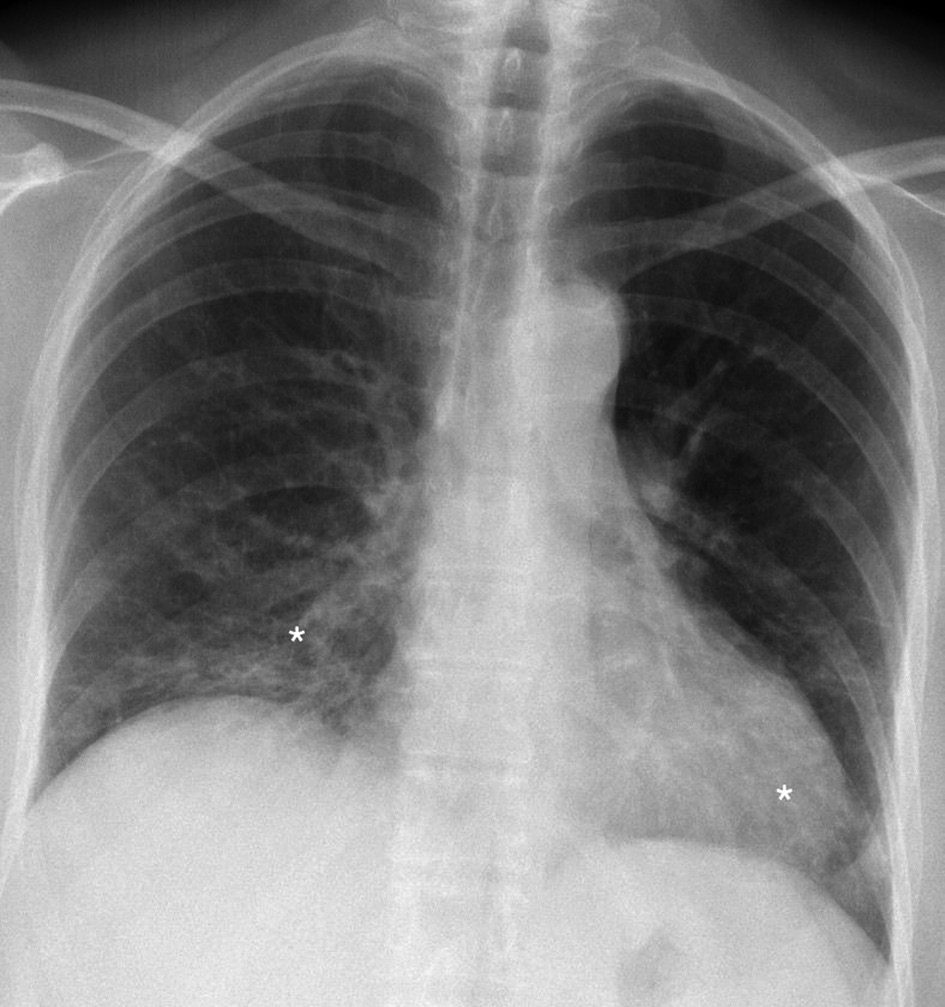

After three months patient revisited for treatment control. Subjective patient symptoms were relieved, exercise tolerance increased slightly. Compared with the previous roentgenogram, Chest roentgenography showed minor positive dynamics mainly in the basal segments, although signs of the interstitial disease remain (Figure 4). In pursuance to avoid adverse events, the oral dose of prednisone was gradually reduced to 15 mg/d for three more months.

Figure 4. Chest roentgenogram (2020.05.06) after three months of prednisone treatment. Signs of interstitium infiltration (white asterisks) are decreased (improvement more pronounced on the left side) than in the control chest roentgenogram.